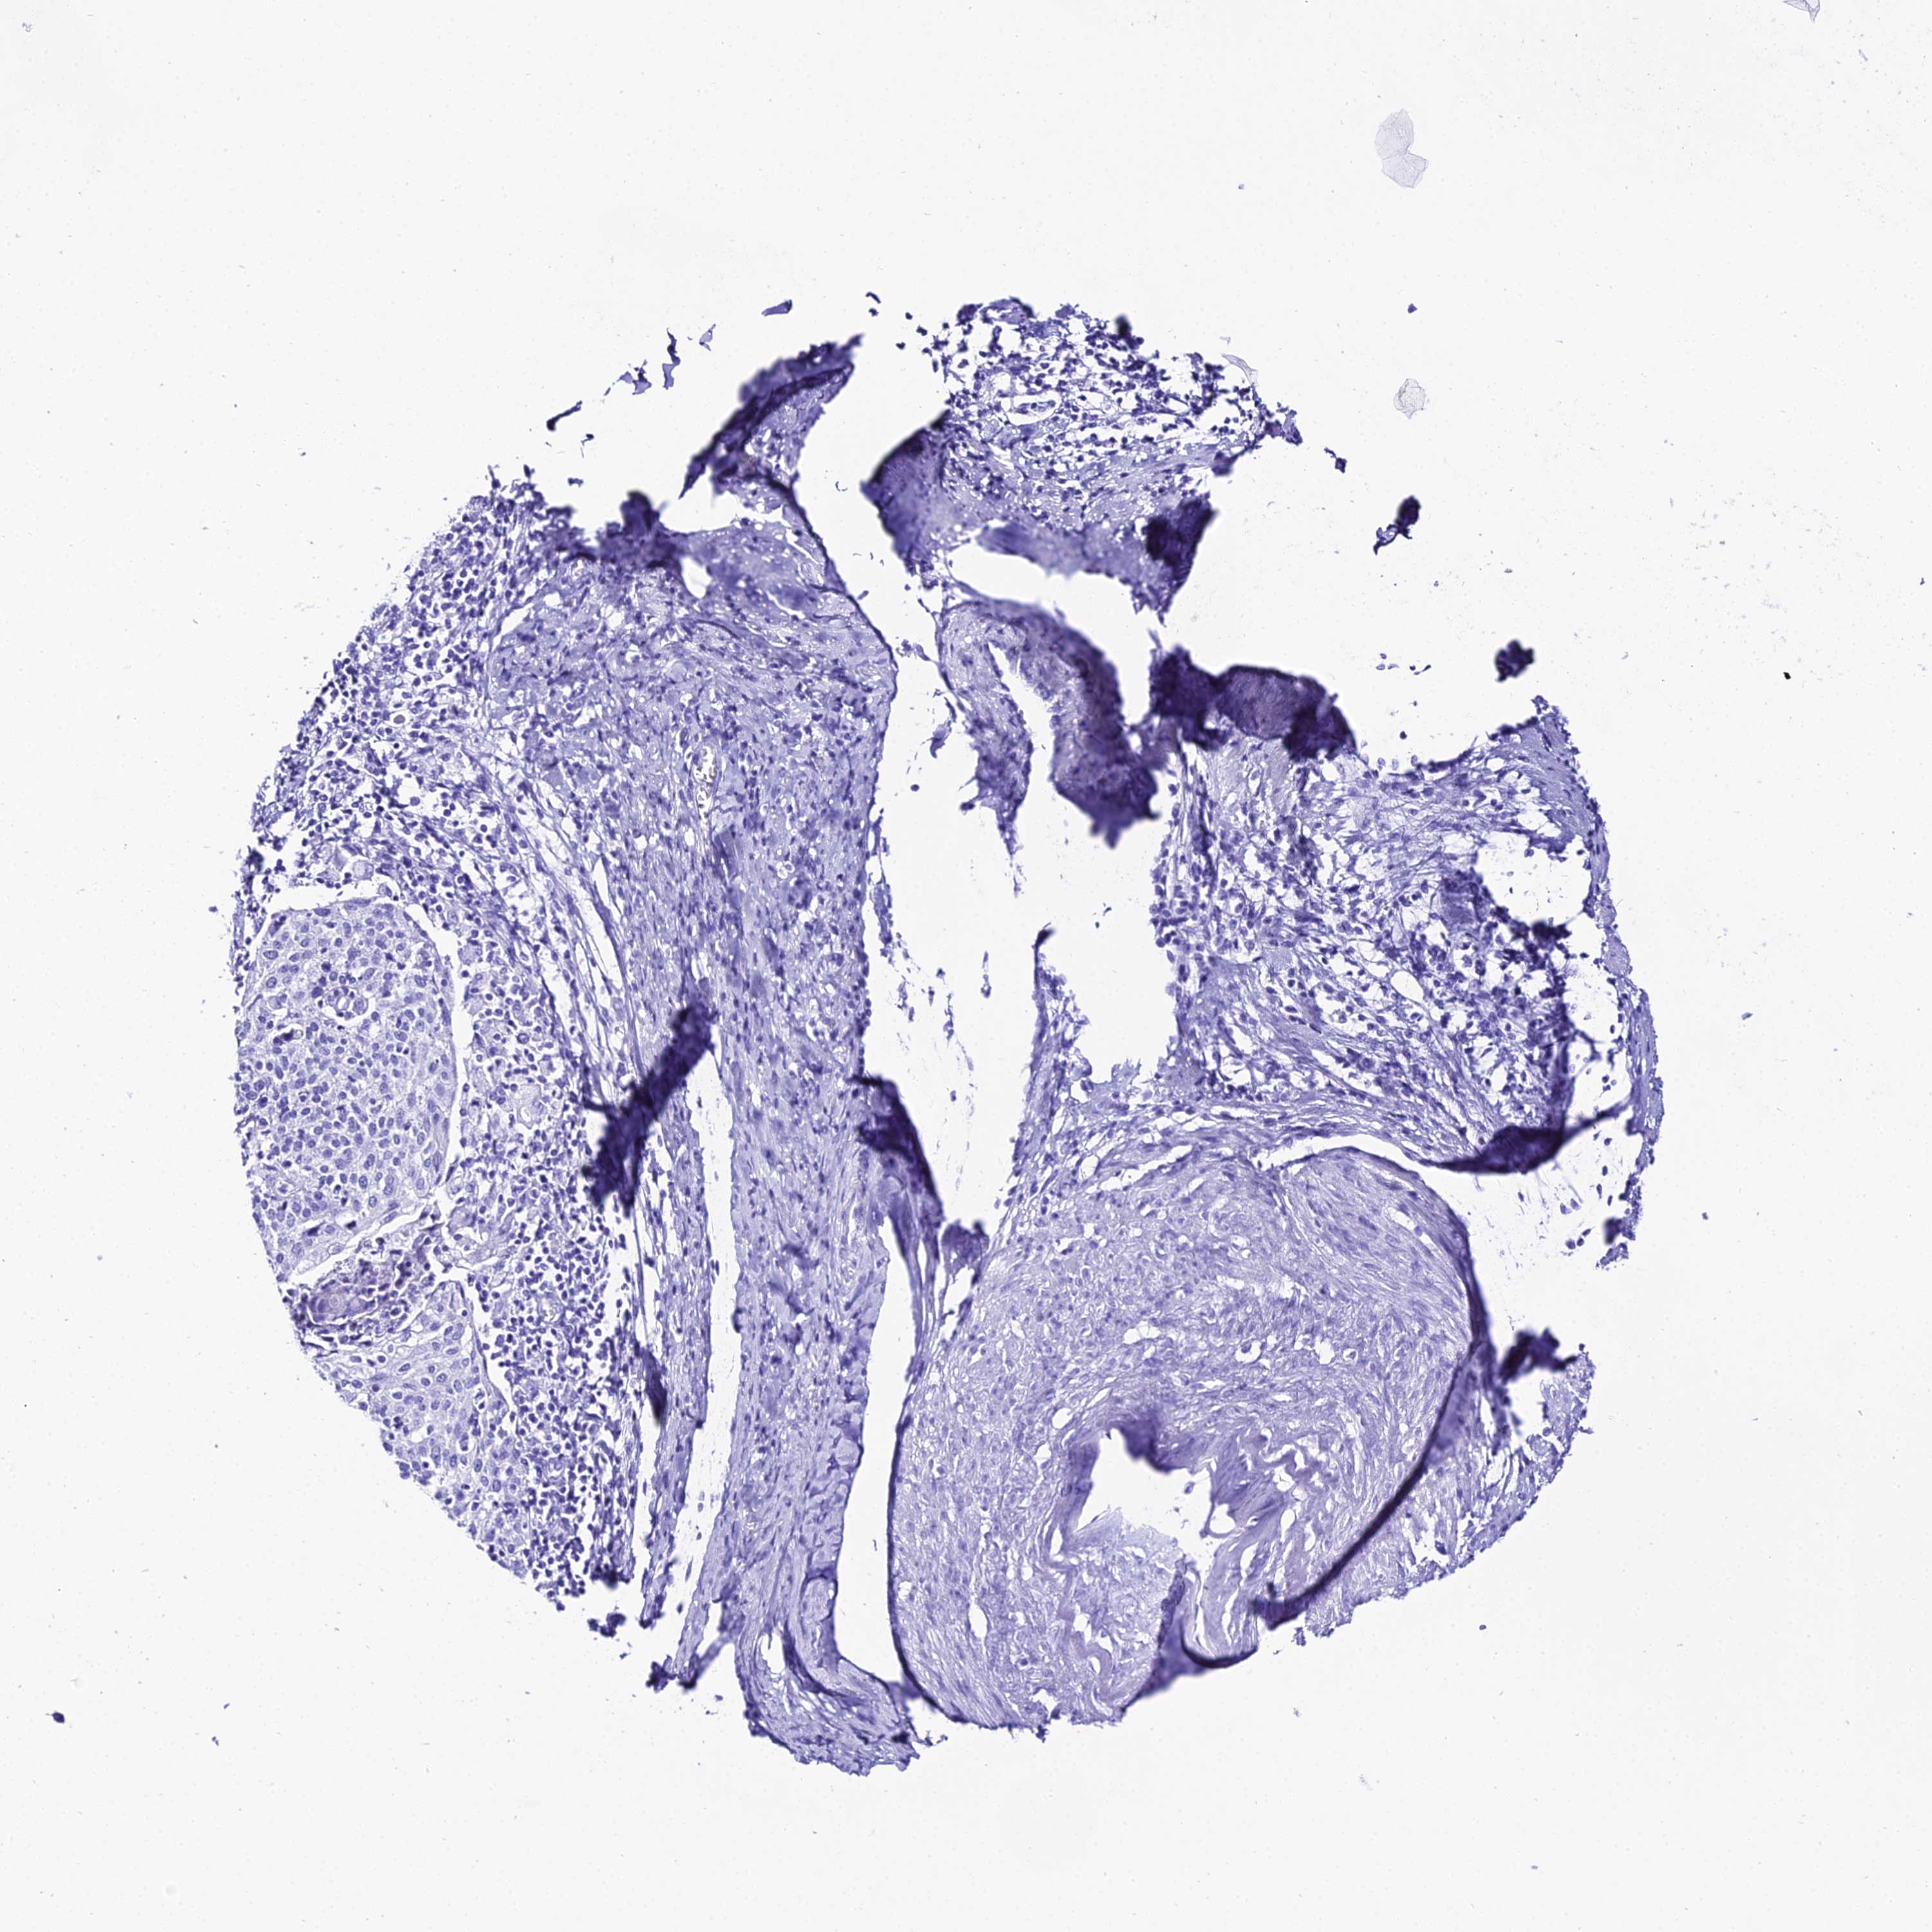

CERVICAL CANCER - Protein expressioni

A mouse-over function shows sample information and annotation data. Click on an image to view it in a full screen mode. Samples can be filtered based on level of antibody staining by selecting one or several of the following categories: high, medium, low and not detected. The assay and annotation is described here.

Note that samples used for immunohistochemistry by the Human Protein Atlas do not correspond to samples in the TCGA dataset.

Antibody stainingi

Antibody staining in the annotated cell types in the current human tissue is reported as not detected, low, medium, or high, based on conventional immunohistochemistry profiling in selected tissues. This score is based on the combination of the staining intensity and fraction of stained cells.

Each image is clickable and will lead to virtual microscopy that enables deeper exploration of all samples and also displays staining intensity scores, fraction scores and subcellular localization as well as patient and tissue information for each sample.

Antibody HPA045461

Staining

High

Medium

Low

Not detected

Intensity

Strong

Moderate

Weak

Negative

Quantity

>75%

75%-25%

<25%

None

Location

Nuclear

Cytoplasmic/membranous

Cytoplasmic/membranous,nuclear

Squamous cell carcinoma, NOS

Adenocarcinoma, NOS